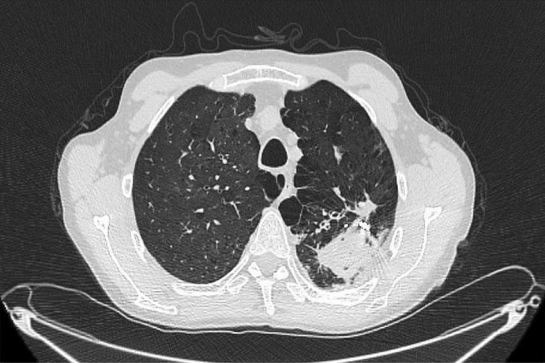

A 59-year-old patient presented to our institution with worsening moderate haemoptysis caused by a recurrent aspergilloma in his left upper lobe (fig. 1). He had a background relevant for previous pulmonary aspergilloma that had been treated with a left thoracotomy and wedge resection of the lower lobe 18 years before. He had a good performance status at his presentation. He was offered surgical treatment with a re-do left thoracotomy and upper lobe upper division segmentectomy, which was performed with no major intraoperative complications and with a blood loss of around 600 ml. He was put on Voriconazole anti fungal treatment from early and for three months post discharge. The postoperative period was initially complicated by prolonged air leaks and pneumonia. On postoperative day 15, the patient acutely developed hypotensive shock with sudden discharge of blood-stained drainage from the chest drain (around 350 ml in less than 1 hour). The chest drain was promptly clamped and, while fluid resuscitation and 3 units of blood were administered, an urgent chest radiography was obtained which confirmed a retained collection in keeping with haemothorax. At that point it was decided to perform an emergency thoracotomy and re-exploration of the pleural space. At surgery, the bleeding source was found to be coming from a 3 mm fistula connecting the lateral wall of the descending thoracic aorta to the pleural space. Since the arterial tissue around the fistula was deemed too frail to sustain direct closure with stitching, the bleeding source was initially controlled with haemostatic patches (Veriset™ Haemostatic Patch, Medtronic© Limited, Watford, UK) and packing of the pleural space with large gauze swabs. Immediately after the surgery, an angio-CT scan was performed and confirmed the presence of an irregular outpouching of the descending aorta corresponding to the known source of the bleeding (fig. 2a).

Fig 2a: Angio-CT scan  was performed and confirmed the presence of an irregular outpouching of the descending aorta- circled.

Figure 2